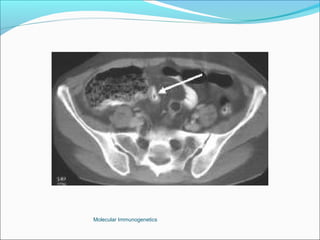

Computer Tomography: More superior to USS in diagnostic accuracy.

The Appendix -Acute Appendicitis Investigations White cell count: high sensitivity 96%, low specificity Urine analysis Plain Xray, nonspecific Ultrasound highly sensitive (80-90%), excludes other pathologies. Computer Tomography: More superior to USS in diagnostic accuracy. Barium enema: Good accuracy, but technically difficult and false positives are common. Laparoscopy Active observation Computer aided diagnosis. Peritoneal lavage Molecular Immunogenetics